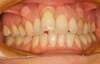

Rédicive d'un traitement dans l'enfance repris avec des gouttières

B-Début 2